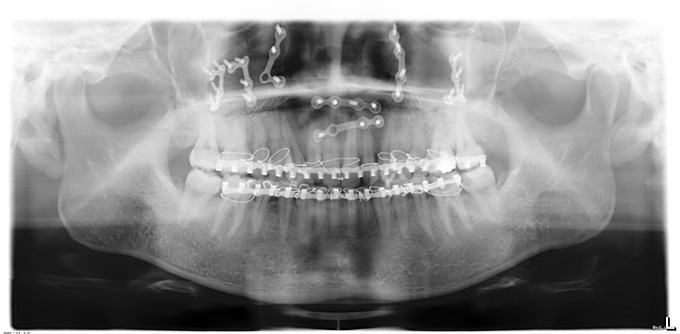

上颌骨骨折术后1年,患者于1年前因车祸骨折于我院行双侧上颌骨、颧骨骨折复位内固定术+上下颌牙弓夹板结扎术+气管切开术。现患者张口度正常,咬合可,今按期返院拆除钛板,门诊以"上颌骨骨折术后钛板存留"收入院

诊断:双侧上颌骨骨折术后钛板存留,全景片示原双侧上颌骨骨质折断区见骨性愈合,金属板存留。无手术绝对禁忌证,于2015年12月17日在手术室全麻下行“上颌钛板、钛钉取出术+邻近瓣转移修复术”。